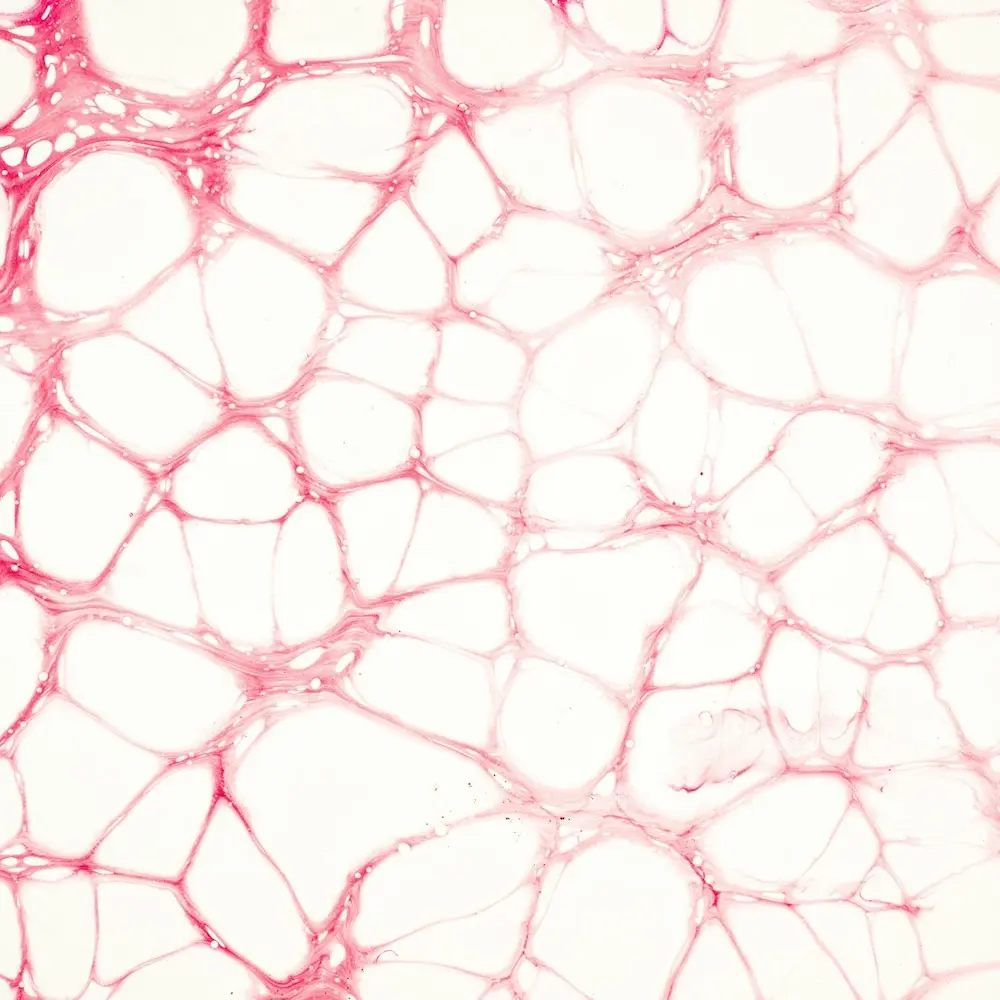

Das Mikrobiom, also die Gesamtheit der im Darm lebenden Bakterien, produziert Vitamine, reguliert Entzündungsprozesse und schützt die Darmbarriere. Gerät dieses Ökosystem aus dem Gleichgewicht, können Beschwerden wie Blähungen, Durchfall, Reflux oder Nahrungsmittelunverträglichkeiten entstehen. Langfristig kann ein gestörtes Mikrobiom sogar das Immunsystem schwächen, Entzündungen fördern und die Entstehung chronischer Erkrankungen begünstigen.Eine gesunde Darmfunktion ist daher entscheidend für Energie, Immunsystem, mentale Stabilität und ein ausgewogenes Wohlbefinden.